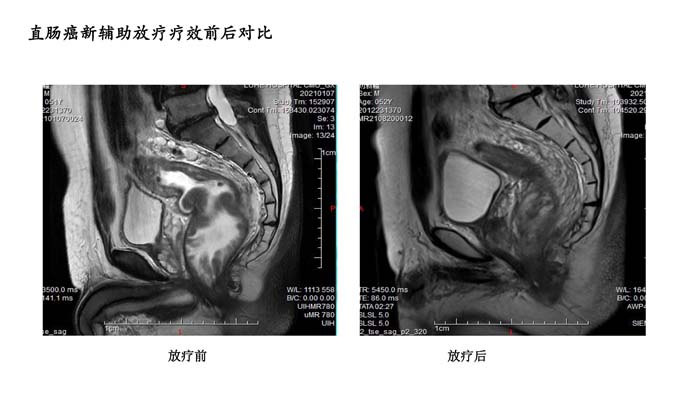

直肠癌新辅助放疗疗效前后对比4